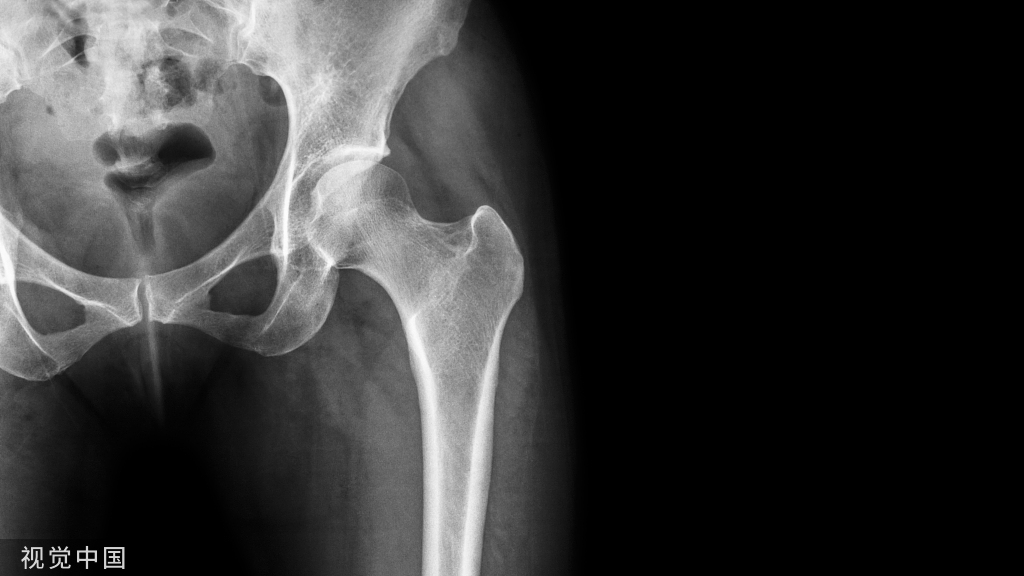

左图45岁 男 布鲁氏杆菌性脊柱炎,X线平片L5椎体前上角侵蚀样骨破坏、呈鸟嘴样,椎间隙真空征(星号);右图54岁 男 布鲁氏杆菌性脊柱炎,X线侧位显示L4/L5椎体前缘呈“鹦鹉嘴Parrots’ beak”样骨破坏。